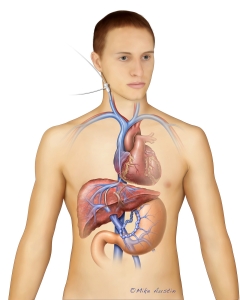

Internal Art Medical Illustration

Blending Art, Anatomy and Science for Creative Visuals

Patient & Professional Marketing

Welcome to my Patient and Professional Marketing page, where I harness the power of anatomical illustrations to educate and empower both patients and medical professionals. My unique approach combines artistry and education to convey complex surgical procedures and the utilization of medical devices in an easily understandable manner.